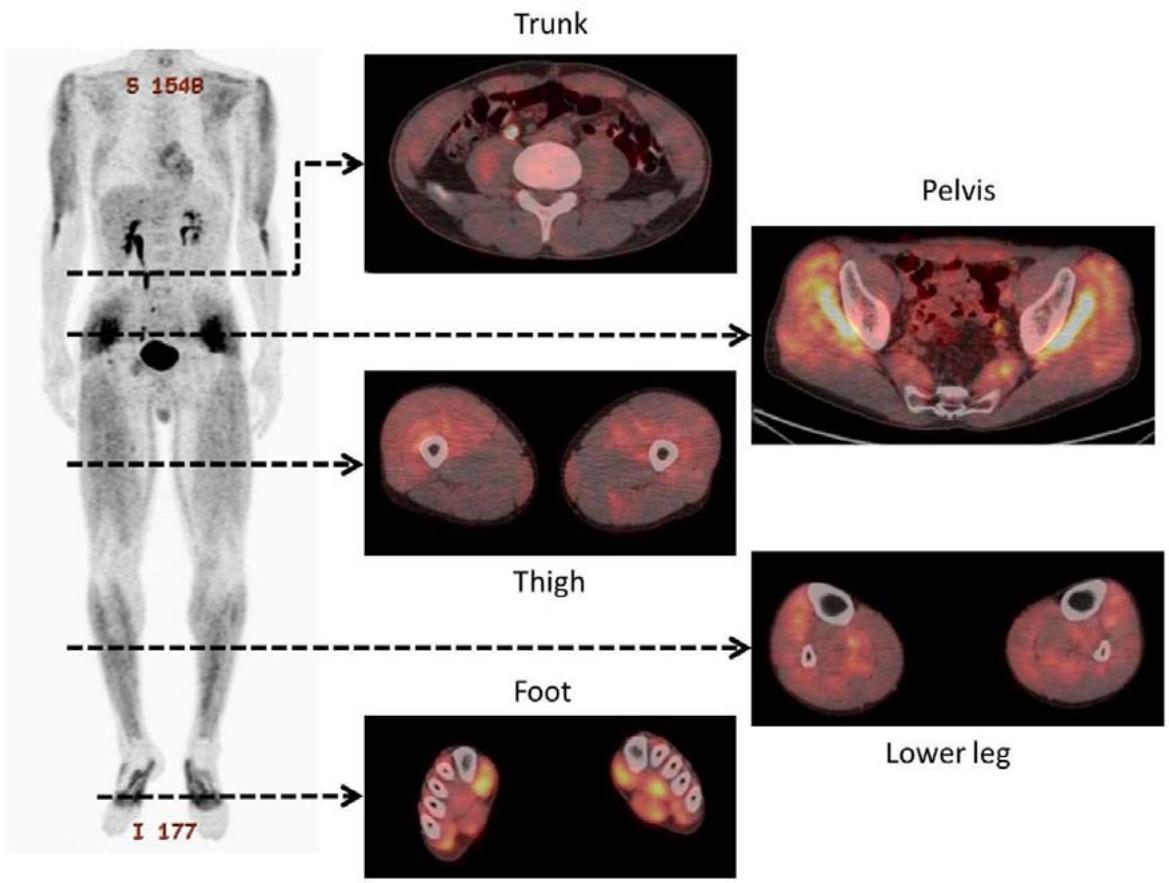

Following our line of thought on hypoxia we would like to add data related to exercise. Exercising subjects can develop hypoxemia (235, 236) and physical activity can lead to HIF activation in skeletal muscle (237). Experimental hypoxia in skeletal muscle of rabbits is accompanied by a reduction of the levels of ubiquinone (130). A decrease of the $\mathrm{CoQ}_{10}$ levels is seen together with diminished ATP levels in isolated rabbit ventricles under hypoxia (Table 2 in (131)). Metabolic changes related to exercise can be seen with diagnostic $^{18}$ F-FDG imaging. Nakase et al., demonstrated focal uptake in football players (238) (Figure 9).

Whole Body Muscle Activity during the FIFA 11+

Figure 9: Taken from Nakase J, Inaki A, Mochizuki T, Toratani T, Kosaka M, Ohashi Y, et al. Whole Body Muscle Activity During the Fifa 11+ Program Evaluated by Positron Emission Tomography. PLoS One (2013) 8(9):e73898. Epub 2013/09/26. doi: https://doi.org/10.1371/journal.pone.0073898. License: Creative Commons Attribution License

doi:10.1371/journal.pone.0073898.g002

Figure 2. Representative whole-body positron emission tomography images after performance of the $11+$ by patients in the exercise group.